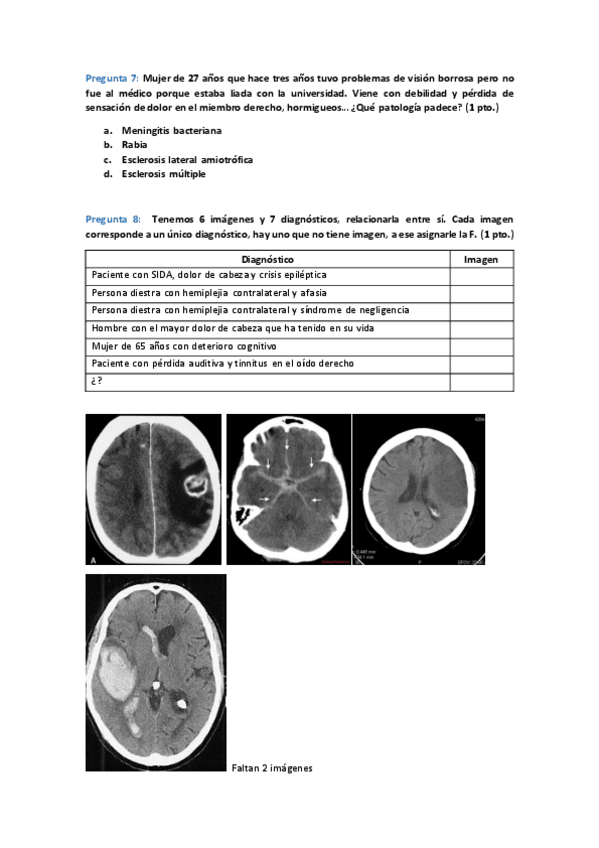

He publicado nuevos examenes de 3º Fisiopatología Humana: 1er-parcial-2021.pdf

He publicado nuevos examenes de 3º Fisiopatología Humana: Examenes-Curso-2020-21.pdf